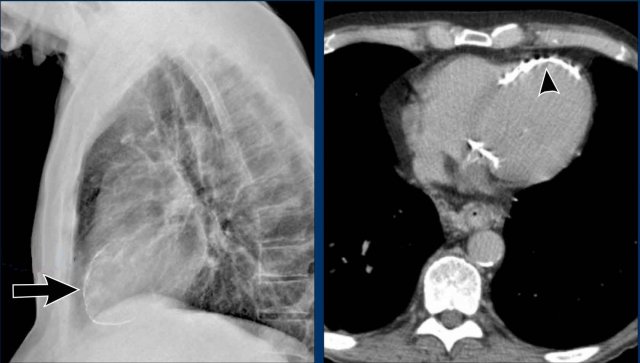

Notice the air within the hernia on the lateral view (black arrow).

Displacement of the Azygoesophageal Line (2) – Subcarinal Lymphadenopathy

A common cause of displacement of the azygoesophageal line is subcarinal lymphadenopathy (station 7).

On the chest X-ray, note superior displacement of the azygoesophageal line just below the carina, consistent with enlarged subcarinal lymph nodes (black arrow).

Additional right paratracheal lymphadenopathy is seen, displacing the right paratracheal stripe (white arrow) and deviating the trachea to the left.

Continue with PET-CT...

PET Imaging

• PET-CT demonstrates extensive hypermetabolic lymphadenopathy in the mediastinum and neck, which is more conspicuous than on chest radiography.

• Cervical lymph nodes are involved—an important finding as they are accessible for biopsy.

Continue with images of CT and ultrasound...

CT Imaging

• Contrast-enhanced CT shows bulky subcarinal lymphadenopathy displacing the azygoesophageal recess and compressing the left atrium.

• Biopsy of a cervical node confirmed small cell lung carcinoma.